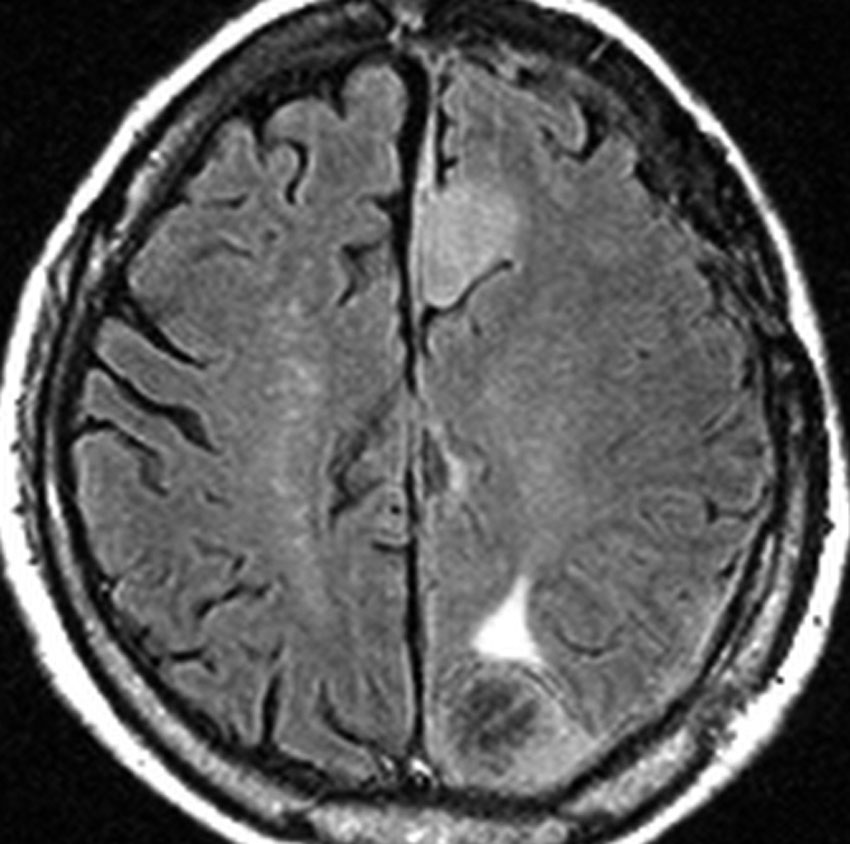

片側髄膜腫症 unilateral meningiomatosis

50歳ころから15年間に3回の開頭手術を受けている患者さんです。parasagittal, falx, convexityなど6個の髄膜腫がすでに摘出されています。左側だけ,テント上だけに髄膜腫が20個くらい多発していました。これらはグレード1で,anaplastic meningiomaの転移ではありません。

やがて蝶形骨縁の髄膜腫の増大速度が早まりatypical meningiomaとなりました。MIB-1 index が10%の高値でした。病理学的にも,psamomatous meningiomaなど様々な種類の髄膜腫が多発しています。

初発時から多発性髄膜腫であり,最初の手術で左側テント上の硬膜を広範囲に摘出しておくべきでした。このような病態は若年者でもみられることがあり,胎生期の硬膜の原基になる細胞にmutationが生じたとしか考えづらいものです。